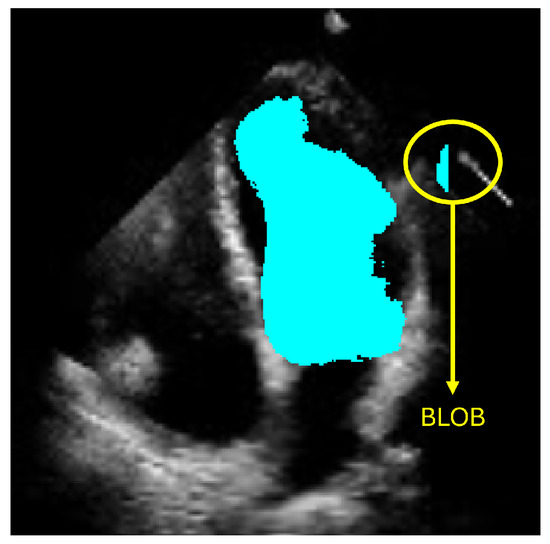

However, accurately defining the LV contour and shape remains a critical challenge for diagnosing heart failure. Computational methods have emerged to support cardiologists in producing more precise and efficient diagnoses. Currently, deep-learning-based approaches, particularly those employing semantic segmentation like convolutional neural networks (CNNs), have shown promising results. Nevertheless, these methods can produce anatomically inconsistent or noisy LV contours, including implausible segmentations with irregular or disconnected regions that do not correspond to the expected LV morphology. Such artifacts, commonly referred to as blobs in medical image analysis, result from pixel-level misclassification errors inherent in semantic segmentation approaches and may significantly compromise clinical reliability. In this work, we address these limitations by presenting a new method for LV segmentation, and the novelty of this work lies in three key contributions. First, we introduce ShapeNet, a specialized ensemble of CNNs that directly predicts both the pose parameters (rotation, translation, and scale) and shape deformation parameters of a statistical shape model, eliminating the artifacts produced by pixel misclassification in semantic segmentation methods (blobs). Second, we develop an improved ASM that optimizes a global objective function based on concatenated gray-level profiles, demonstrating superior capture range and robustness compared to traditional ASM approaches. Third, our fully automatic pipeline uniquely combines these components to generate anatomically plausible contours, without manual initialization—a significant advantage over semi-automatic methods like BEASM [3]. This integrated approach maintains the flexibility of data-driven deep learning, while utilizing the anatomical validity offered by shape models, as evidenced by our consistent performance across both CAMUS and independent EchoNet datasets.

3. Materials and Methods

The objective of ShapeNet is the accurate characterization the left ventricle contour through the prediction of optimal pose (rotation, translation, and scale) and shape (deformation vector) parameters for a trained point distribution model (PDM) of the LV in echocardiography. This is achieved by training a CNN with the aforementioned parameters of the PDM that have been accurately adjusted to the left ventricle on each image of the training set. This approach prevents the formation of blobs produced by pixel classification errors in semantic classification, preventing correct characterization of the LV, as illustrated in Figure 1. In contrast, our approach consistently produces statistically valid contours of the left ventricle, which are accurately adjusted by means of the improved ASM proposed in this paper.

Figure 1.

Example of blobs produced by misclassification in semantic segmentation of the left ventricle.